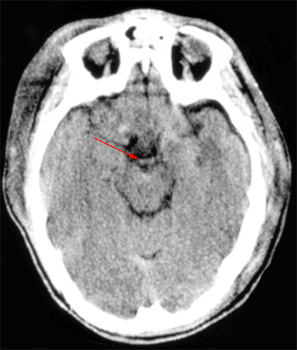

Head CT > Infection > Basilar Thrombosis

Basilar Thrombosis

Thrombosis of the basilar artery is a common finding in stroke patients. CT findings include a dense basilar artery without contrast injection.

![]() ![]() The arrow in the

left CT indicates the dense basilar artery. Compare this to the normal |